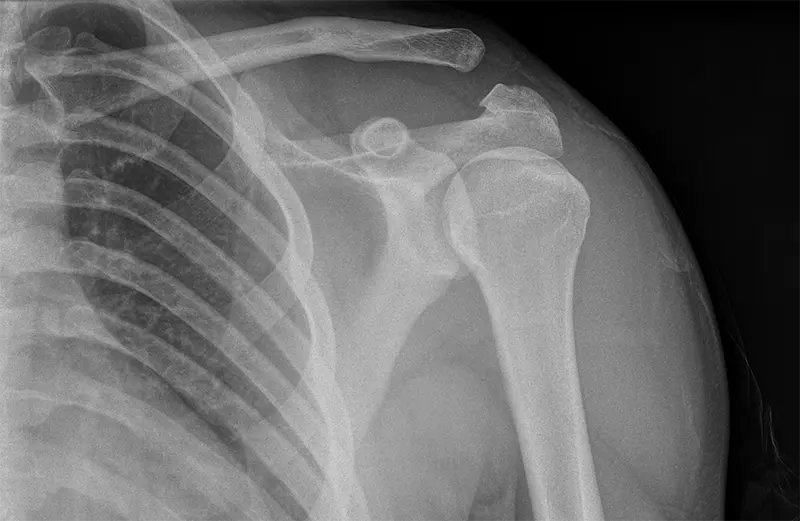

Rekonstrukcja więzadła barkowo-obojczykowego

Rekonstrukcja więzadła barkowo-obojczykowego to zabieg, który ma na celu zmniejszenie diastazy barkowo-obojczykowej. Procedura ta odgrywa kluczową rolę w zapobieganiu opadaniu kończyny górnej oraz zmniejszeniu przestrzeni barkowo-obojczykowej.

Diastaza barkowo-obojczykowa często jest wynikiem urazów, takich jak upadek na ramię. Procedura rekonstrukcji więzadła barkowo-obojczykowego może znacząco pomóc w redukcji diastazy i sprzyja gojeniu więzadeł w ciągu pierwszych 3 tygodni od urazu.